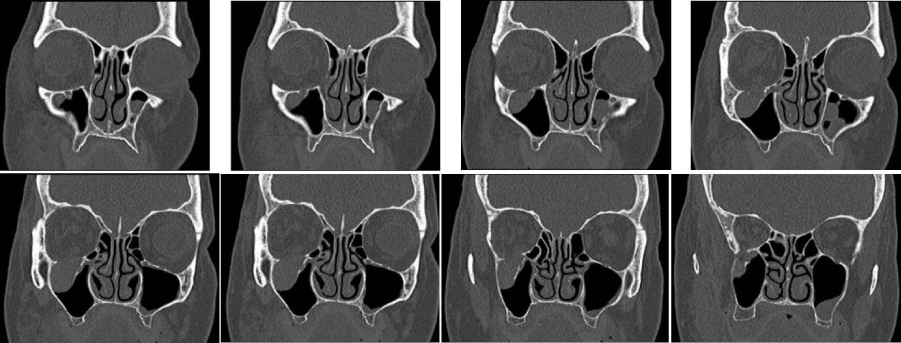

Figure 2:

Samples of study-CAT-scans of patients aged 70+ showing minimal/below critical-size-defect dislocations of isolated zygoma-tripod and/or arch-fractures and related fractures of the orbital-floor.

Figure 3:

Samples of study-CAT-scans of patients aged 70+ showing above critical-size-defect dislocations of isolated zygoma-tripod and/or arch-fractures and related fractures of the orbital-floor.